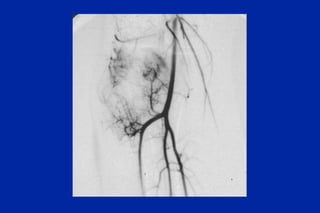

Este documento resume los principales tipos y técnicas de angiografía. Describe brevemente la angiografía, arteriografía, flebografía y linfografía, así como las técnicas de contraste y materiales utilizados. También explica los principales accesos vasculares, la técnica de Seldinger, la angiografía por sustracción digital y algunas técnicas endovasculares comunes.